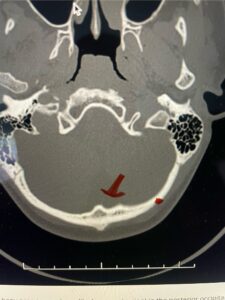

Fig. 4b: Axial T2-weighted cervical MRI demonstrating severe spinal cord compression from atlanto-axial instability (red arrow)